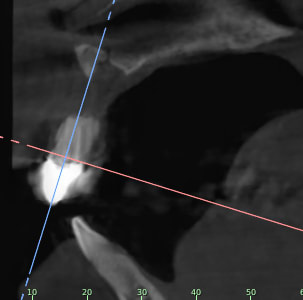

Je rajoutes quelques coupes et une rétro... C'est vraiment un massacre à la tronçonneuse!

24/04/2019 à 15h19

D'autres coupes et une rétro